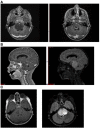

Over the past decade, we have made considerable progress in establishing diffuse intrinsic pontine glioma (DIPG) as a disease entity and developing preclinical tools to interrogate potential therapeutics. However, translation to improved clinical outcomes in children with DIPG has not yet been realized. This is in part due to difficulties encountered in delivering active drugs adequately to the tumor site. However, most preclinical evaluations gloss over the fundamental concepts of central nervous system (CNS) pharmacokinetics and requirements needed to optimize drug delivery and exposure and translate this into efficacious therapy. This article discusses not only the blood:brain barriers but additional barriers to drug delivery for CNS tumors and pharmacokinetic principles that need to be addressed and considered.